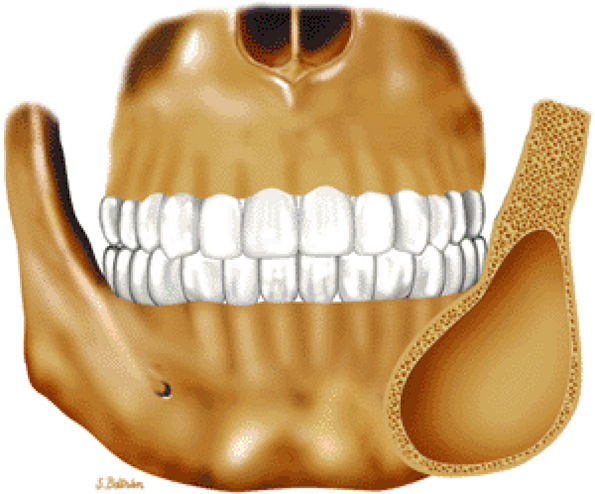

FIGURE 14-43 ● Fibrous dysplasia of the facial bones. Coronal graphic illustration shows an expansile, well-defined lesion involving the angle of the mandible.